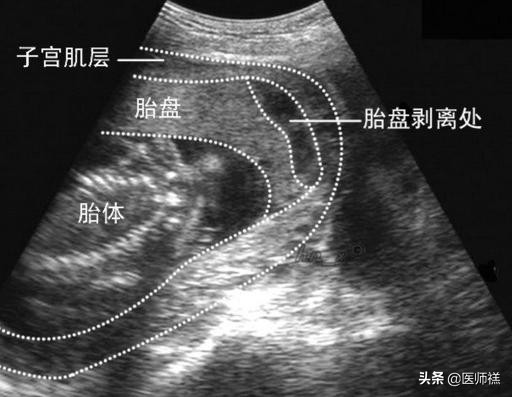

- 3、胎盘早破:由于多胞胎的缘故,宫腔压力往往较高,存在10%以上的几率引发胎盘早破。